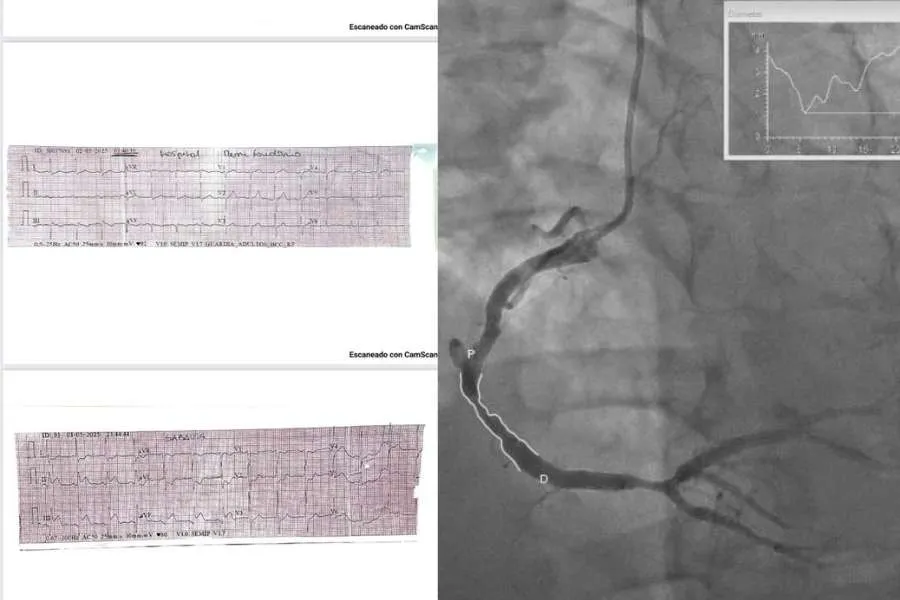

En un hecho inédito para el sistema de salud pampeano, el pasado jueves se realizó por primera vez en la historia de La Humada un tratamiento fibrinolítico para un infarto agudo de miocardio. La intervención fue posible gracias a la activación del “Código Infarto” mediante el sistema de telemedicina Cardio 365, lo que permitió aplicar el protocolo de atención en tiempo real, con el acompañamiento de un cardiólogo desde Santa Rosa.

La Humada, localidad del oeste con cerca de mil habitantes y ubicada a 400 kilómetros de la capital provincial —de los cuales 80 km son de ripio—, fue escenario de este hito sanitario. El paciente ingresó con un infarto de cara inferior y, tras la rápida intervención del equipo médico local, se le administró estreptoquinasa, una medicación clave para disolver coágulos. Es la primera vez que este tratamiento se realiza en La Humada, una de las localidades más alejadas de la capital pampeana.

En diálogo con InfoHuella, el subsecretario de Salud, Gustavo Vera, detalló que, tras recibir la medicación, el paciente fue derivado en ambulancia con acompañamiento médico. El recorrido incluyó paradas en los hospitales de Santa Isabel y Victorica, hasta arribar finalmente a Santa Rosa, donde se le practicó un electrocardiograma post estreptoquinasa que mostró una evolución favorable. Fue internado en terapia intensiva y, 48 horas después, se le realizó una angioplastia con éxito. Hoy se encuentra en sala común, en recuperación.